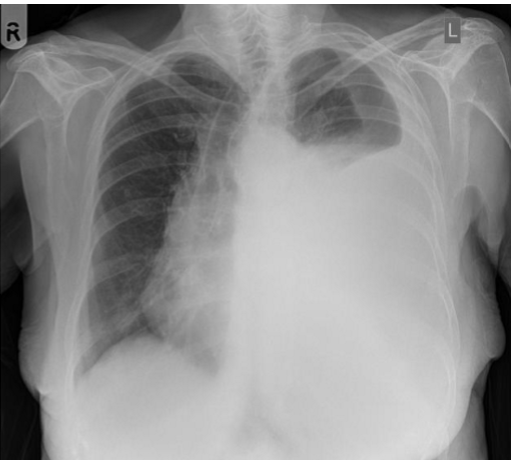

What is going on in these pictures. Whats the dx?

Left pic: normal

Right pic: COPD